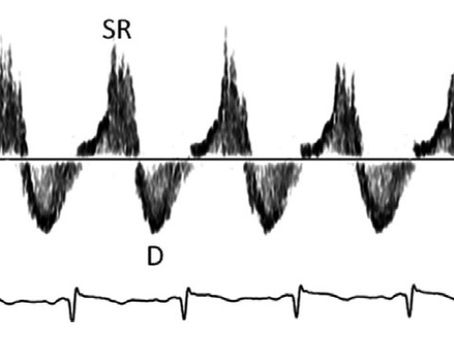

DOPPLER DE VENAS HEPÁTICAS EN TRASTORNOS DEL RITMO CARDIACO

Spectral Doppler of the Hepatic Veins in Rate, Rhythm, and Conduction Disorders. Echocardiography. 2016 Jan;33(1):136-40....